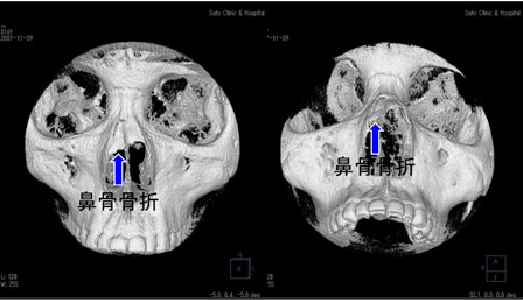

鼻骨骨折とは

鼻骨骨折とは、鼻の上半分を構成する鼻骨に生じる骨折のことを指します。鼻骨は薄い骨であり、顔面に対しての外力をきっかけとして骨折が生じやすく、比較的頻度の高い骨折です。肘が当たるなどの軽微な外力で生じることが多いですが、時に、より大きな外力が加わることによって鼻骨以外の部位にも同時に骨折が生じることもあります。

鼻骨骨折が生じると、骨折が生じた部位に痛みが生じます。局所を押さえると痛みは増強し、鼻血も同時に見られます。骨折によって鼻骨の形が変形してしまい、外から見た際に鼻が歪んで見えることもあります。

鼻骨の変形に関連して、空気の通り道としての鼻の穴の大きさに著しい左右差が生じてしまい、鼻が詰まったような感覚や、息苦しさを覚えることもあります。また、骨折を生じた部位周辺に出血斑やむくみが生じることもあります。